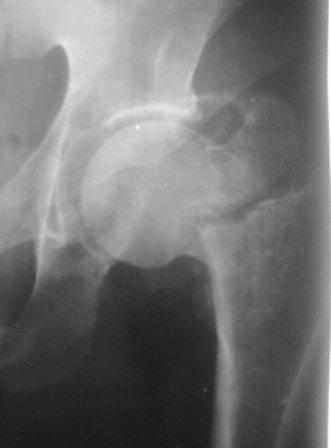

Больной 1980г.р. после тяжелой сочетанной травмы от 03.12.10г:

спленэктомии, ушивание разрыва печени, мн.переломы ребер. 05.02.11г

операция по поводу спаечной к/непроходимости.  И чрезвертельный

перелом правого бедра, посмотрел под скопией сращения нет, при

проверке двигается только дистальный отломок, а головка как бы

припаяна к вертлуге. Укорочение ноги 5см, нога ротирована вовнутрь и

приведена, из-за боли проверить обьем движения не удается.

В плане PFN -ChM , но может быть контрактура т/б сустава, или делать

открытым   способом (тогда большая кровопотеря, и так он

ослабленный), м/б предварительно аппарат таз-бедро или вытяжение

большим грузом.?